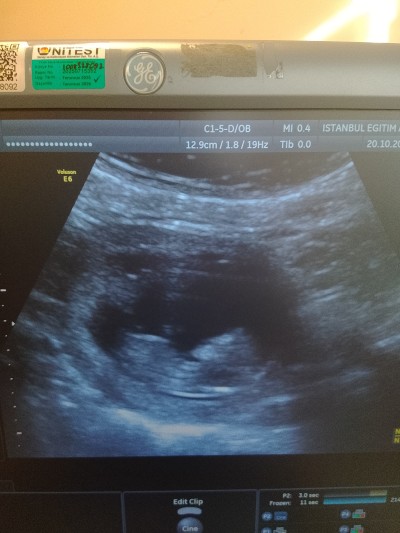

Kizlar cinsiyet için daha erken ama ben yinede merak ettim ama bı tahminde bulunabilir misiniz :) tabiki öncelik sağlıklı olması kız erkek farketmez ama insan yinede merak ediyor 11+4 haftalık

Ultrason fotoğrafını benimkine benzettim cinsiyetimiz kız. Hayırlı sağlıklı olsun

Kız canım yüz şêkli anımsattı cene yapısı kız çocukların sivri olur derler hayirlisi

Nub çıkıntısı bize gösteriyor ki bu bir kız 🥰